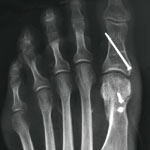

Abb. 2

Hallux vor Korrektur